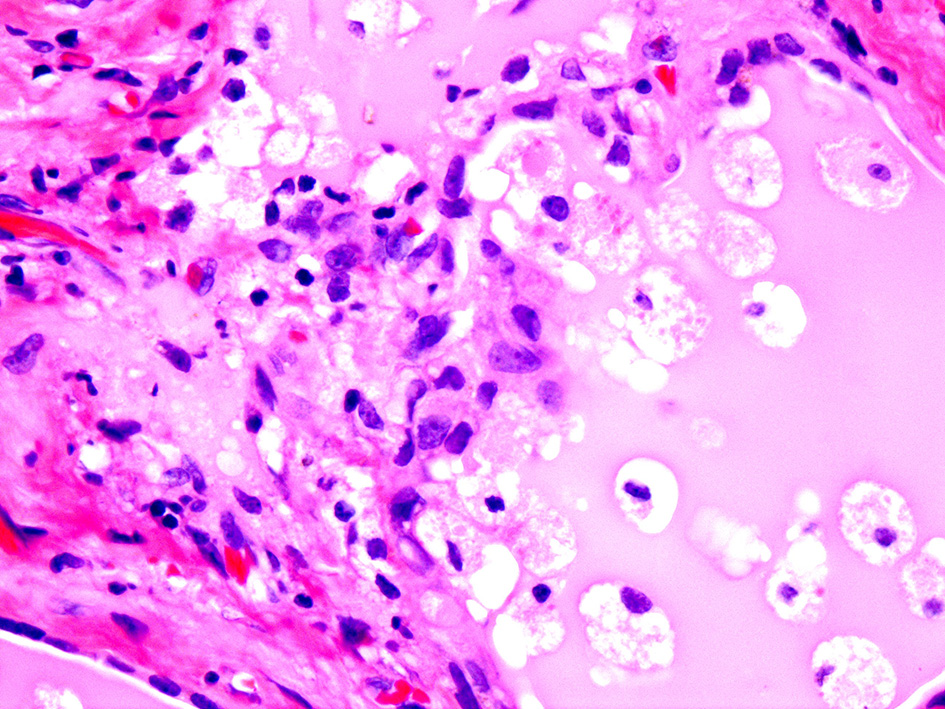

If the gland is already pathologically abnormal (nodular thyroid goiter, Graves' disease), the pathology of the resected gland shows follicular disruption with histiocytes infiltrating the follicular epithelium and colloid (Figures 5, 6). Rarely, inflammatory cells are noted within the thyroid parenchyma (Type I). On the other hand if the thyroid is histologically normal (Type II), the pathologic lesions show much milder follicular damage (73–75). These changes are similar to those seen in amiodarone induced pulmonary and liver toxicity (76, 77). Ultrastructural studies of both lung and thyroid tissues have shown lysosomal and mitochondrial inclusions in follicular cells consistent with follicle cell destruction (77). However, this simple explanation is not the only reason for the thyroid dysfunction. For example, co-cultures of amiodarone with human thyrocytes have shown the production of interleukin 6 and the drug also decreases the sodium-iodide symporter mRNA in the follicular cells (78).

Figure 5. Amiodarone associated follicular cell damage. Low and high power showing large thyroid follicles filled with colloid and numerous histiocytes (arrow heads, 3A,B).

Figure 6. Same as Figure 5.